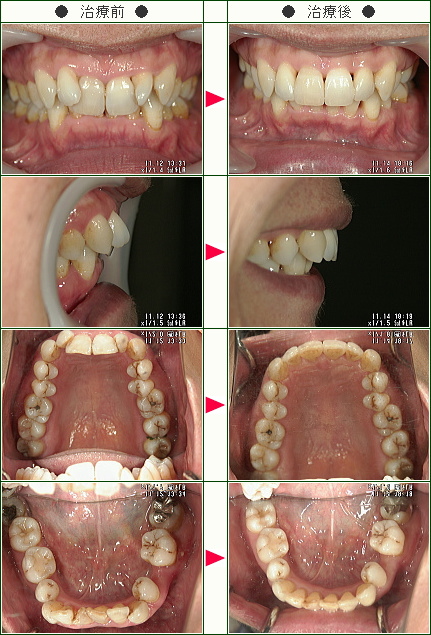

「歯を抜くと言われ逃げ帰って以降、私には矯正は無縁のものと思っていました」K.K.様 60歳 女性

中学生のころから矯正をしたいと思っていましたが、一度、歯医者さんで相談したところ、歯を抜くといわれ、逃げ帰りました。

それ以降、私には矯正は無縁のものと思っていました。

昨年秋に、何気なく、ホームページ検索をしていた時「大人の矯正」という文字が目に入り、大人でも矯正できるのかと思い、ホームページの中をじっくり読ませていただきました。

その後、思い切ってTELをして青山院長に相談したら、抜歯しなくても矯正できるとお聞きして、早速治療をお願いしました。

先生はじめ、スタッフの皆様に大変親切に接していただき、本当に良かったと思っています。

ありがとうございました。